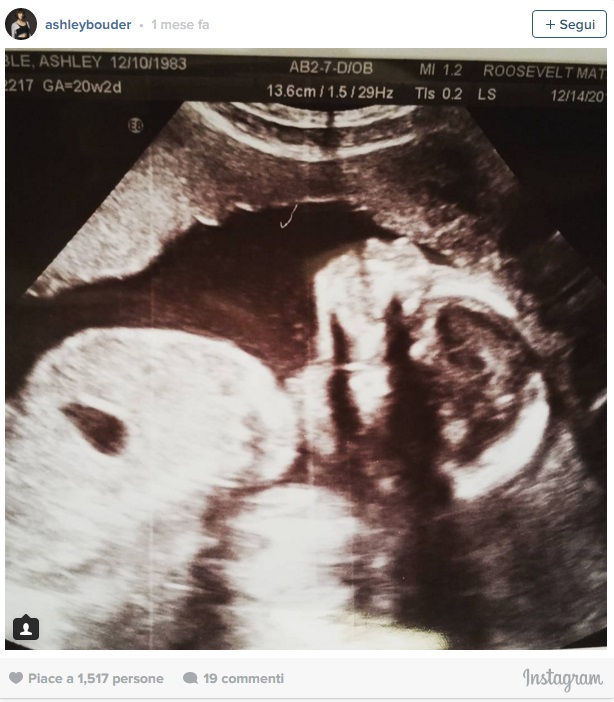

Ashley ha annunciato la sua gravidanza ai fan lo scorso novembre, attraverso la foto della radiografia postata su Instagram. L’immagine è stata subito condivisa con questa didascalia: “Lei ha già il naso del papà, non vedo l’ora di conoscerla”.